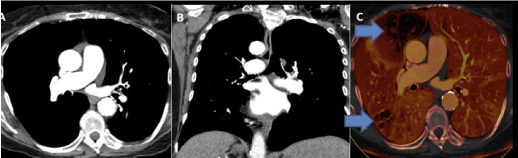

Figure 1. DECT characterization of excretory organ stones. A. DECT axial image shows left excretory organ calculus (stone) with attenuation of 825 HU at one hundred forty kVp. B. This image has 1250 HU attenuation at eighty kVp. C. The stone was firm to be composed of calcium oxalate monohydrate victimization DECT post process algorithms. Reprinted with permission from Coursey CA, Nelson RC, Boll DT, et al. Dual-energy multidetector CT. Radiographic. 2010;30(4): 1045.Uric acids stones demonstrate exaggerated photons attenuation at a hundred and forty kVp as a result of the attenuation is driven primarily by Compton scatter (due to lighter 30% chemical composition).